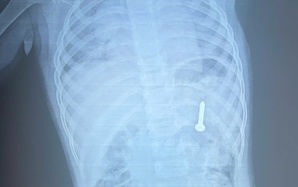

Người phụ nữ ợ hơi, tức ngực đến bệnh viện phát hiện điều bất ngờ

(NLĐO) - Bị ợ hơi sau ăn rồi tức ngực cách đây 2 năm, người phụ nữ đi điều trị nhiều nơi nhưng bệnh tình không thuyên giảm.